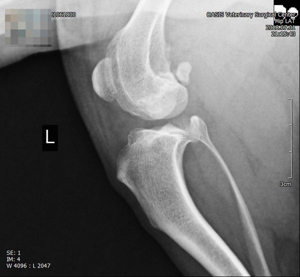

진단 방법

- 임상 증상과 이학적 검사(무릎의 불안정성 확인)

- 방사선(X-ray) 촬영

- 관절 초음파 검사 등 영상 진단